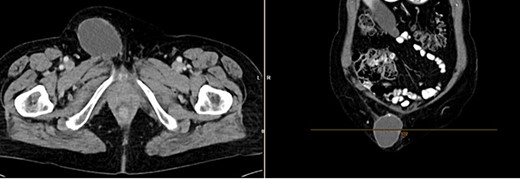

Further clarification was sought through a computed tomography (CT) scan of the entire abdomen (Fig. 1). The CT from 25 February 2022 showed an oval, encapsulated structure in the right groin area, most likely interpreted as a soft tissue hematoma. No active bleeding was observed. An enlarged lymph node was considered as a differential diagnosis. A follow-up CT on 1 August 2022 showed a size-progressive formation within the suspected right inguinal hernia compared with the previous examination in February (Fig. 2). There was no evidence of tumor recurrence or metastasis-suspect lesions intra-abdominally. A previous hysterectomy was also noted.

CT of the abdomen from 25 February 2022: oval encapsulated structure in the right groin area, most likely soft tissue hematoma, no active bleeding, DD enlarged lymph node.